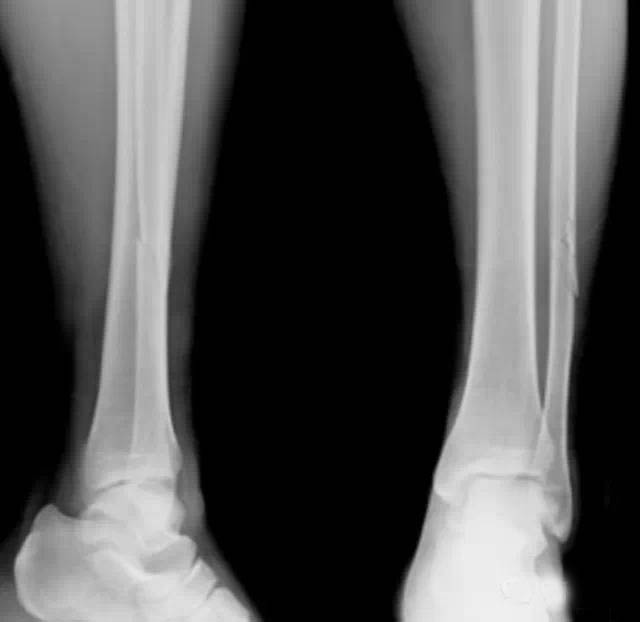

胫腓骨骨折是临床非常常见的一种骨折,因为胫腓骨位于小腿,实际上人体小腿部分有两根骨头,一根是粗的骨头,叫胫骨;一根是细的骨头,叫腓骨。

胫腓骨骨干骨折在全身骨折中最为常见。10岁以下儿童尤为多见。其中以胫骨干单骨折最多,胫腓骨干双折次之,腓骨干单骨折最少。胫骨是连接股骨下方的支承体重的主要骨骼,腓骨是附连小腿肌肉的重要骨骼,并承担1/6的承重。胫骨中下1/3处易于骨折。胫骨上1/3骨折移位,易压迫腘动脉,造成小腿下段严重缺血坏死。胫骨中1/3骨折淤血潴留在小腿的骨筋膜室,增加室内压力造成缺血性肌挛缩。胫骨中下1/3骨折使滋养动脉断裂,易引起骨折 延迟愈合。

胫腓骨肩负着行走和负重的功能,在日常工作和生活中容易遭受损伤。胫腓骨骨折为人体最常见的长骨骨折之一,约占全身骨折的8-12%,且多为双骨同时骨折,因胫骨前软组织覆盖较少,开放性骨折多见